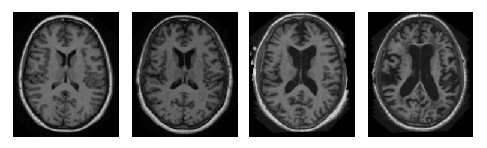

There are three major stages in Alzheimer’s Disease - very mild, mild and moderate. Detection of Alzheimer’s Disease (AD) is still not accurate until a patient reaches moderate AD. But early detection and classification of AD are critical for proper treatment and preventing brain tissue damage. Alzheimer’s disease has a certain progressive pattern of brain tissue damage. It shrinks the hippocampus and cerebral cortex of the brain and enlarges the ventricles [13]. Hippocampus is the responsible part of the brain for episodic and spatial memory. It also works as a relay structure between our body and brain. The reduction in hippocampus causes cell loss and damage specifically to synapses and neuron ends. So neurons cannot communicate anymore via synapses. As a result, brain regions related to remembering (short term memory), thinking, planning, and judgment are affected [13]. The degenerated brain cells have low intensity in MRI images [14]. Figure 1 shows some brain MRI images presenting different AD stage.

Figure 1: Example of different brain MRI images presenting different AD stage. 1 Nondemented; 1 very mild dementia ; 1 mild dementia; 1 moderate dementia.